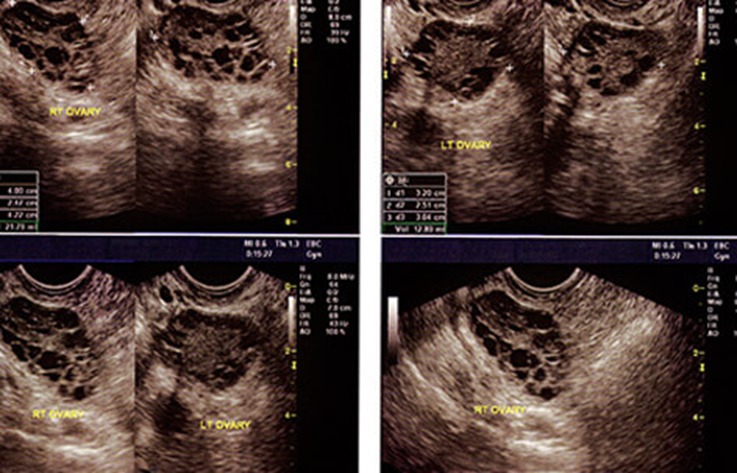

Распознать и диагностировать рак яичников довольно трудно. Это связано в первую очередь с расположением яичников в брюшной полости, что исключает возможность зрительного контроля. Основным методом является УЗИ органов малого таза.